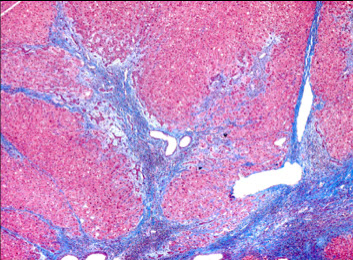

Alcoholic cirrhosis

Caused by recurrent bouts of alcoholic hepatitis, this is the final, irreversible form of liver dz

- liver is micronodular and small from scarring

Sx: Jaundice, edema (hypoalbuminemia)

Micro: sclerosis around central vein (zone III); Councilman bodies (necrotic liver cells); bridging fibrous septa linking portal tracts, fibrosis, parenchymal nodules